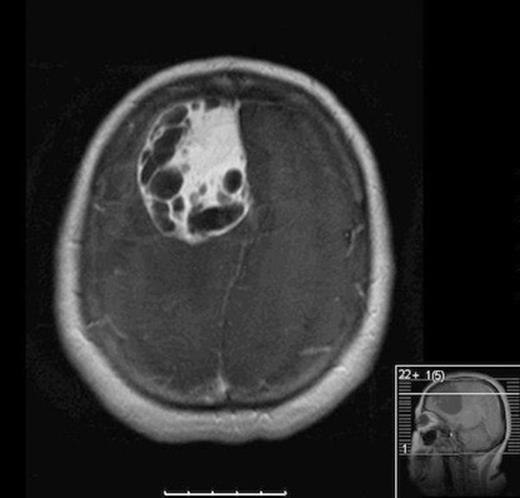

Post-operative MRI showing gross-total resection with some residual blood in cavity

She was taken to the operating the following morning for a bicoronal craniotomy for a gross-total tumor resection with neuronavigation (Fig 2). Pathology was a dural-based WHO Grade 1 supratentorial haemangioblastoma. Microscopic findings demonstrated large vessels and abundant capillary networks, with a cellular proliferation of large stromal cells with clear vacuolated cytoplasm (Fig 3,4,5). There were significant hyperchromatic nuclei and multiple areas of PAS positive pinkish globules (Fig 3,4,5).